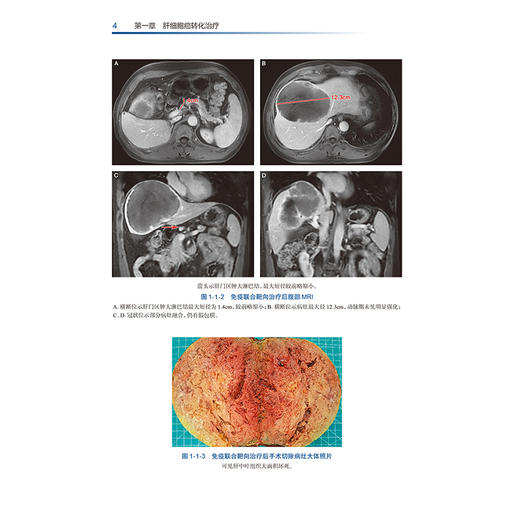

本专著主要包括5个主题,读者对象为肝胆外科医生、肿瘤内科的各年资医生。具体如下:【1】肝细胞癌转化序贯外科治疗:主要内容为晚期原发性肝癌(特指CNLC-Ⅲ期以上或巴塞罗那分期C期以上)患者或初诊时残肝体积不足的患者,接受免疫联合治疗以达到转化效果,再次获得手术指征,并接受包括同种异体肝脏移植或肝脏切除术在内的外科手术以达到肿瘤根治的方案介绍与示例详解。【2】肝细胞癌新辅助治疗:主要内容为对初诊时具备手术指征但临床判断为适宜先行新辅助治疗的肝细胞癌患者,因为新辅助治疗可使得患者远期预后更佳,并且手术更加简单可行。本部分主要涉及到对于新辅助治疗的指征,判断患者新辅助治疗深度与手术时机选取的案例。【3】难治性复发肝癌的免疫联合治疗:主要包括外科或局部治疗术后肝内出现多个复发病灶且复发病灶的数量≥3个;肝内复发病灶累及主要的血管,如侵及肝静脉、门静脉或血管内形成癌栓;出现肝外扩散及远隔转移如肺、骨、脑转移等;出现腹腔内多发淋巴结转移;侵犯肝脏邻近组织及器官或腹腔种植性转移。该方案可控制肿瘤进展并为患者争取手术根治性切除机会,大大提高了患者的生存时间,展示了一种新型治疗模式。【4】其他肝胆系统肿瘤的免疫联合治疗探索:本部分对于包括肝内胆管细胞癌、胆囊癌在内的肝胆系统其他肿瘤性疾病接受免疫联合治疗以达到转化或新辅助治疗效果为目的的治疗进行了探索,并对典型案例进行报道。【5】免疫联合治疗方案的全程管理:因免疫联合治疗方案需要全程管理患者,在本主题中,除了序贯外科治疗方案牵涉的要点外,额外增加免疫联合治疗过程中多个细节问题的处理。如不良反应的监测与处理,耐药或进展的局部叠加治疗与药物联合方案的更换,难治性复发肝癌的免疫联合治疗要点等方面的案例解析。